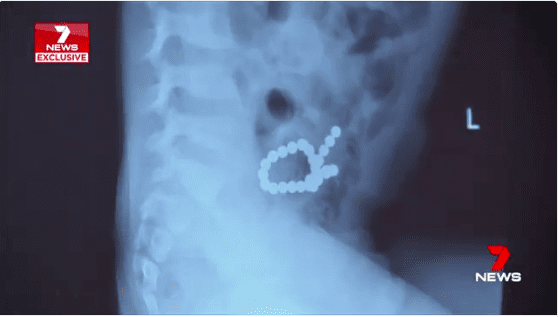

Successivamente le lastre hanno dimostrato che il piccolo aveva ingoiato 30 magneti mentre si trovava sotto la custodia della nonna e questi avevano viaggiato nel suo stomaco per unirsi.

Secondo il dottor Maurizio Pacilli, che ha avuto in cura Noah, i magneti si erano attratti l’uno con l’altro.

Il piccolo ha dovuto affrontare un’operazione di 6 ore. I chirurghi hanno dovuto riparare 10 o 12 buchi a chi hanno dovuto dare dei punti uno alla volta.

Inoltre è stata rimossa una parte dell’intestino.

“I magneti possono danneggiare seriamente lo stomaco e l’intestino attraendosi l’un l’altro attraverso diversi circuiti dell’intestino. Infine i magneti possono causare una mancanza di sangue negli strati interni e punture nei rivestimenti dell’intestino. Questo è ciò che è accaduto a Noah” sostengono gli esperti.